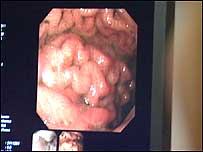

Dr Martin Phillips a liver specialist at the Norfolk and Norwich University Hospital, warns that the health problems are escalating, and women are dying from what used to be a disease mostly affecting older men. "Here in my hospital I am treating women in their 20s and 30s, who are dying from cirrhosis." He fears a drink disease epidemic over the next 15 years if women don't take advice on drinking. Help at hand | | Counting the cost - an unhealthy liver |